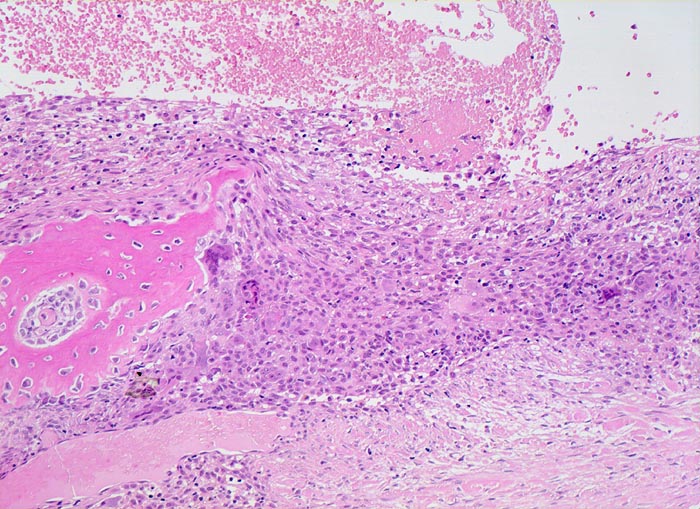

Die AKZ ist charakterisiert durch kavernöse Bluthohlräume mit dazwischengelegenen zellreichen Septen unter Einschluss von Riesenzellen. Da sekundäre AKZ häufig sind, muss das gesamte Material histologisch untersucht werden.

• Pseudozystische kavernöse Bluthohlräume eingebettet in Skelettmuskulatur.

• Die bindegewebigen Pseudozystenwände enthalten solide Massen von mononukleären histiozytenartigen Zellen mit eingestreuten mehrkernigen osteoklastären Riesenzellen.

• Neugebildeter reaktiver Faserknochen mit Osteoblastensaum in der Peripherie der Hohlräume.